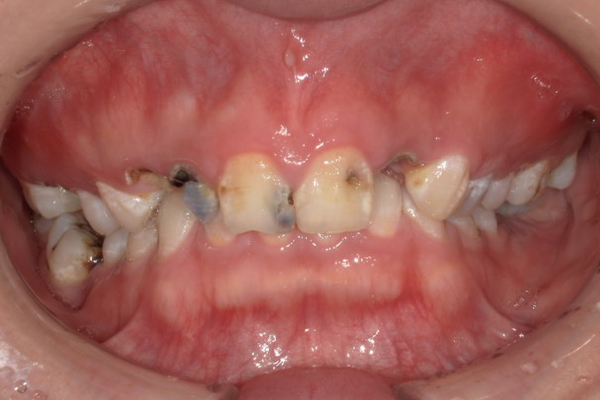

CASE1

セラミックを用いた虫歯治療

| 主訴 | 虫歯の治療と全体的な見た目の改善 |

|---|---|

| 治療期間 | 2ヶ月 |

| 治療費 | セラミック1本 88,000円〜165,000円(税込) デンタルローンで月3,000円から始められます |

| 治療の リスク | 治療には神経の治療や抜歯が必要な場合があります。 虫歯や歯周病を防ぐ為に、定期検診にご来院いただきます。 |